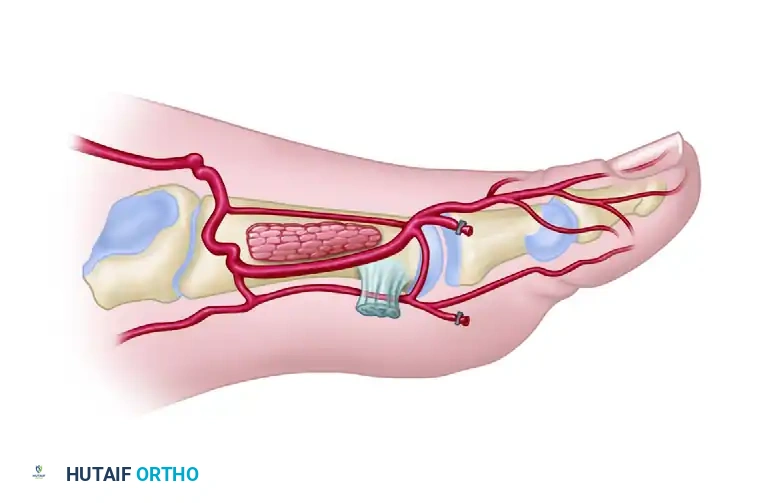

- Retract the EHL tendon medially to expose the periosteum overlying the first metatarsal.

- Identify the dorsalis pedis artery (DPA), its accompanying venae comitantes, and the deep peroneal nerve.

- Continue the dissection laterally and distally to trace the DPA. Identify the origins of the first dorsal metatarsal artery (FDMA), the arcuate artery, and the deep plantar (communicating) artery.

- Once the deep plantar artery is definitively identified plunging plantarly, carefully ligate and transect it. This mobilizes the distal DPA and FDMA.

- Continue dissecting distally, maintaining the plane superficial to the paratenon over the EDL tendons.

- Identify the extensor hallucis brevis (EHB) tendon, which crosses obliquely over the DPA.

- Surgical Option: The EHB tendon can be transected and carried with the flap. However, leaving the EHB muscle belly on the foot can provide valuable vascularized coverage over the underlying bone and tendons, improving the donor site bed.

- As dissection proceeds distally into the first web space, keep the FDMA superficial to the plane of dissection, ensuring it remains attached to the skin paddle.

- Ligate and divide the distal arterial branches to the toes at the distal margin of the flap.